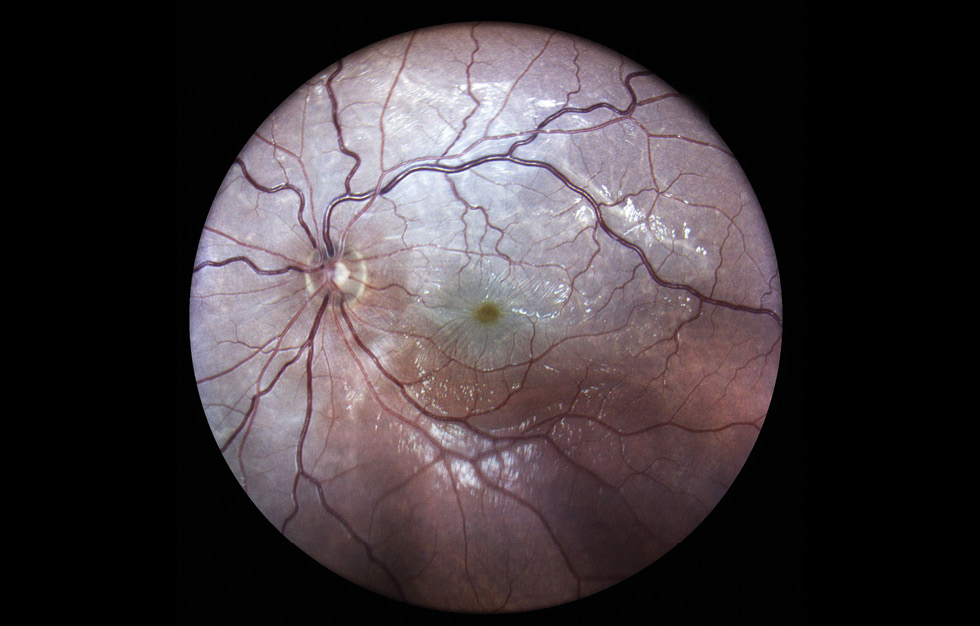

RESULTS: This article presents the clinical case of postoperative choroidal detachment in a child with Sturge–Weber–Crabbe syndrome after microinvasive non-penetrating glaucoma surgery. Against the background of the existing anomalies in the development of an optic disc after antiglaucomatous intervention for decompensated glaucoma, after the normalization of IOP, the patient developed choroid detachment with exudative retinal detachment the next day of operation. After conservative therapy involving bed rest and double instillation of mydriatics for 1 month, the situation was completely resolved and his vision was restored to 1.0.

DISCUSSION: The atypicality of our clinical case of CD lies in the overly pronounced exudative component. In addition to the classic CD vesicles, we observed high exudative retinal detachment as well as high retinoschisis, which is extremely atypical for classical CD. Considering the characteristics of congenital syndrome, it is necessary to accurately differentiate atypical CCA from the rare choroidal effusion syndrome, which also includes CCA with retinal detachment, but does not present with retinoschisis. Against the background of conservative therapy with bed rest and two instillations of mydriatics for 1 month, the situation was completely resolved, and the patient’s vision was restored to 1.0. In the treatment of such patients, it is always necessary to consider their individual anatomical features as well as to understand the detailed pathogenesis of the complications that arise before rushing to repeat surgery.